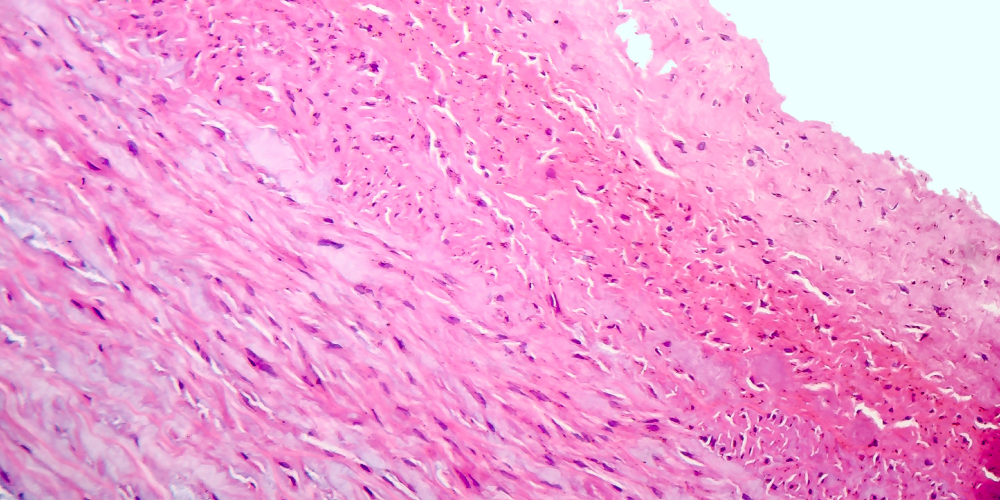

La gangrena de Fournier es una infección genital rápidamente progresiva, afecta la piel, tejido subcutáneo, fascia superficial, produce necrosis hística y severa toxicidad. Es una infección a flora mixta de la zona perineal, producido por gérmenes del tipo de enterobacterias y Bacteroides F.